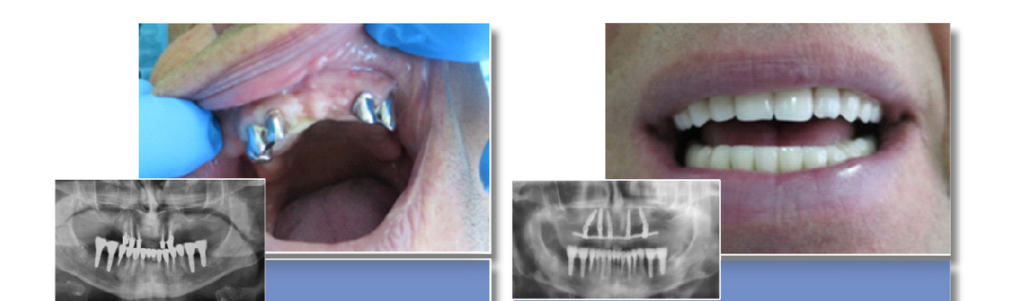

All on 4

All on 4 può creare una serie completa di denti utilizzando solo quattro impianti in ciascuna mascella. La fattibilità di ciò dipende dalla mascella e dalle circostanze specifiche. Una volta valutati i tuoi denti attuali, il livello di danno, nonché la struttura e la salute della mascella, possiamo stabilire se un impianto All on 4 è la scelta giusta. Questa procedura chirurgica utilizza otto impianti, quattro nella mascella superiore e quattro nella mascella inferiore, per supportare protesi o corone permanenti.